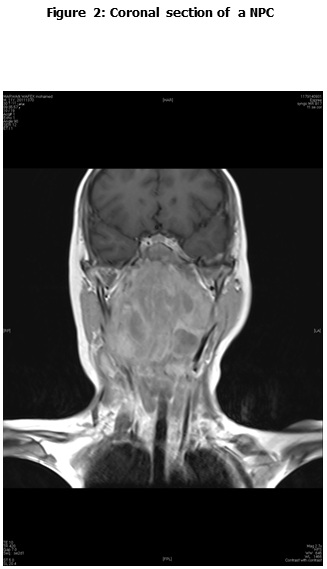

Complete Response (CR): complete disappearance of the tumor confirmed.

Response to Treatment:

Following induction chemotherapy, the overall response rate (CR and PR) was seen in 19 patients (73%); (4 patients (15.3%) achieved CR, 15 (57.6%) PR. Five patients (19.3%) had SD and 2 patients (7.7%) had PD. Whereas, at time of final analysis, 18 patients (69.2%) achieved CR, 5 patients (19.2%) had PD (4 deaths (15.3%), and 1 patient (3.8%) alive under palliative treatment), and 3 patients (11.5%) lost follow up. Table 2 describes patient's response to therapy.

CR 4 (15.4%) 19 (73%) 18 (69.2%)